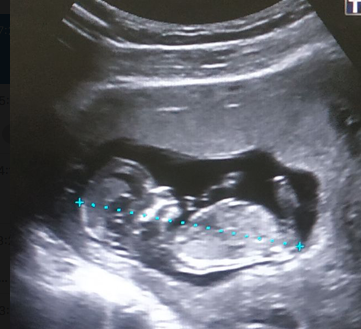

Сходила на скрининг в 12 недель, никакого сообщения о предполагаемом поле ребенка даже не ждала в государственной ЖК, и в целом ориентируюсь на УЗИ в 16 недель, которое я планирую сделать в ЦИРе.

Но все равно очень интересно, поэтому предлагаю вам погадать на двенадцатинедельном УЗИ -- как вам кажется, кто это у нас тут?)) И вообще, видно ли хоть какой-то бугорок на этом фото, а то я вообще не специалистка в рассматривании УЗИ-снимков)

Меня сегодня смотрели в ЦПСиР ииии кажется очень похоже на наш предполагаемый пол , девочка !)))